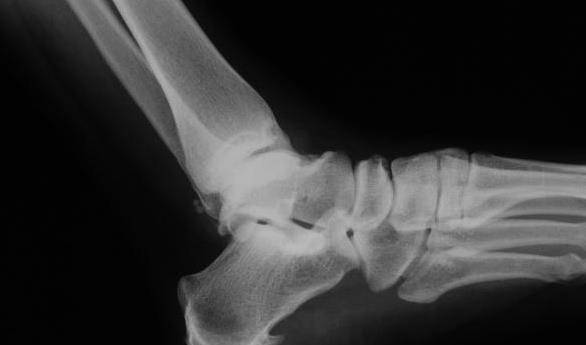

3、骨刺

骨刺也有一个流行的名字 , 叫做骨质增生 , 虽然这是身体老化的自然变化 , 但它确实会引起身体的强烈不适 , 一般发生在老年人身上 , 严重的话也会影响到整个人的移动能力 , 但它基本上是一种不能完全治愈的疾病 , 只有通过自己的日常生活才能更好地缓解疾病 。